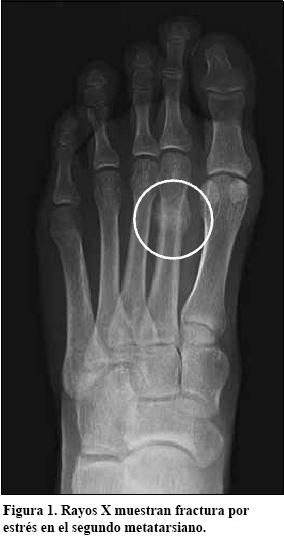

Para confirmar una fractura por tensión, puede que su médico le ordene una radiografía (ver Figura 1). Si la radiografía no muestra una fractura por tensión, puede necesitar realizar una gammagrafía ósea (ver Figura 2) o una resonancia magnética (IRM).